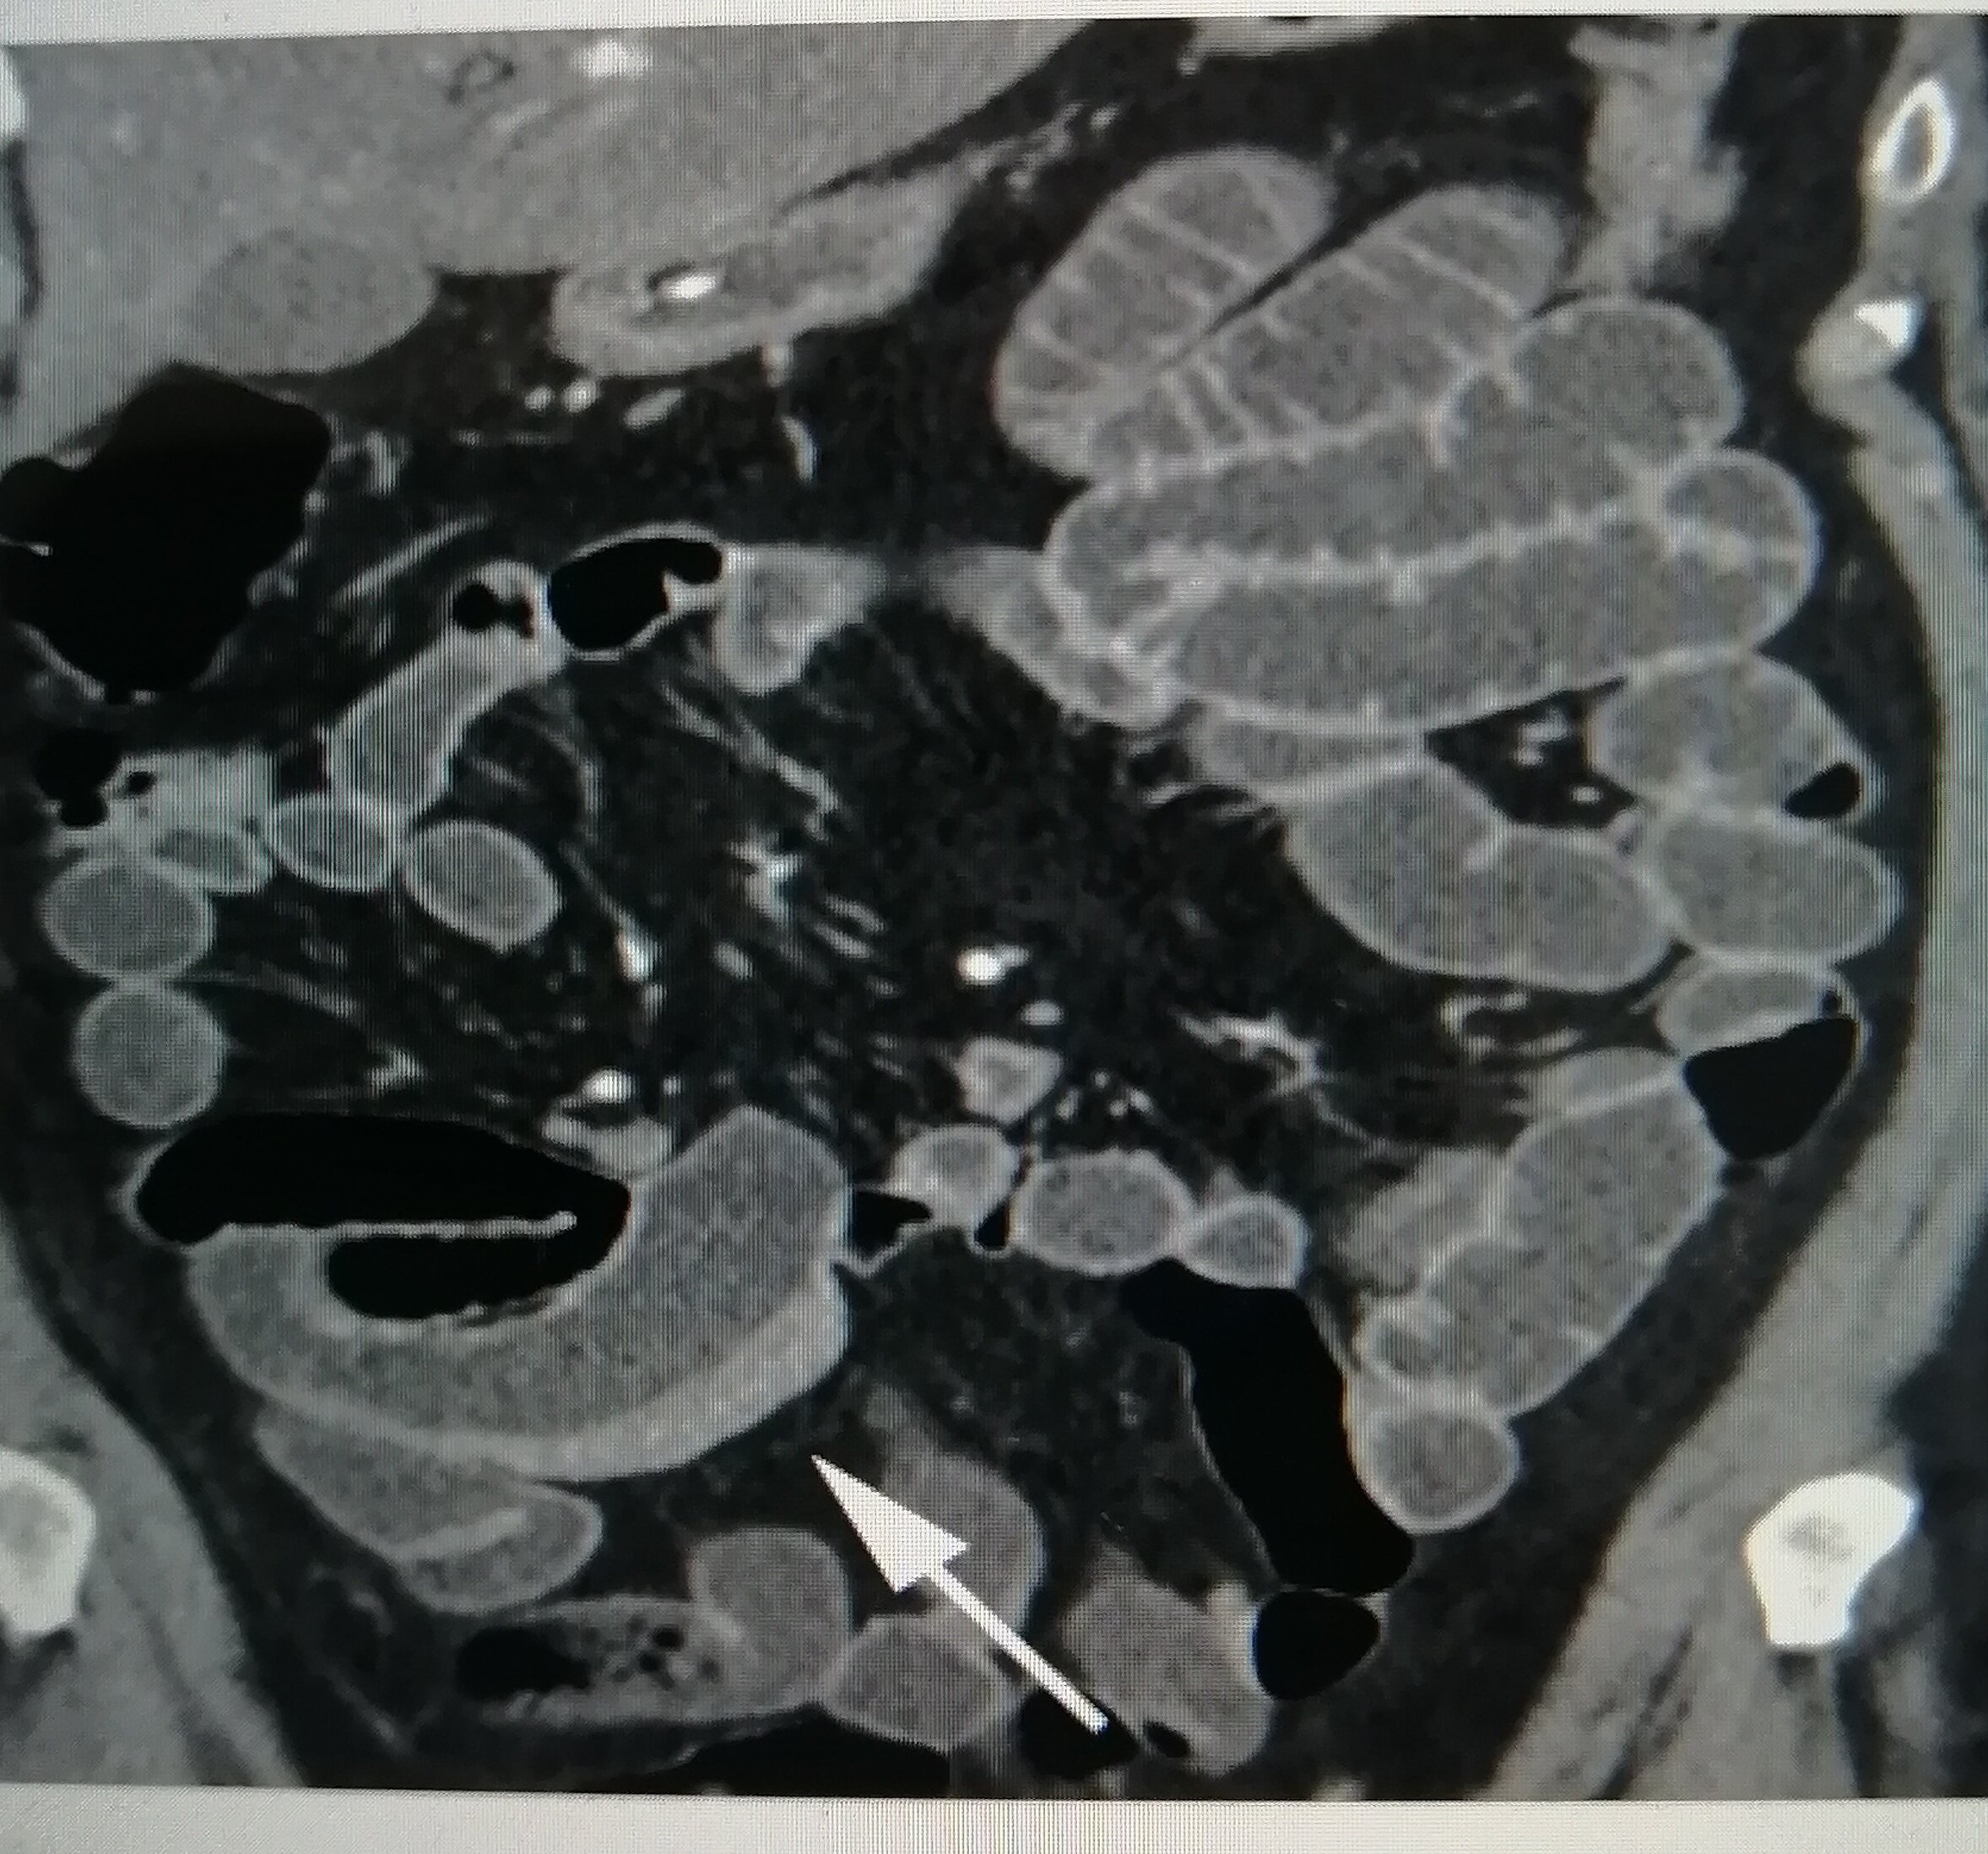

但是,医生们可不是随便下结论的。他们得仔细看看,你是不是真的得了克罗恩病。首先,他们会问你一大堆问题,比如肚子疼多久了,有没有拉肚子,体重有没有下降之类的。然后,他们会让你做一些检查,比如验血、做肠镜,甚至有时候还要做CT或者MRI,看看肠子里到底发生了什么。

关键是,克罗恩病和其他一些病很像,比如溃疡性结肠炎,或者是一些感染性的肠病。所以,医生们得非常小心,不能搞错了。